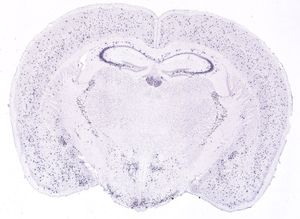

신경계에서는 주로 시상하부의 복내측핵에 위치한 신경분비세포에서 생산된다. 이 세포들은 정중융기를 통해 뇌하수체 문맥계로 소마토스타틴을 방출하여, 뇌하수체 전엽에서의 성장 호르몬(GH)과 갑상선 자극 호르몬(TSH) 분비 조절에 관여한다.[27] 이 외에도 궁상핵, 해마, 뇌간의 고립로핵 등 중추 신경계의 다른 영역에서도 소마토스타틴이 생성된다.

소마토스타틴은 시상하부 외에도 중추 신경계의 다른 영역에서도 생성된다. 대표적으로 궁상핵(arcuate nucleus),[11] 해마,[12] 그리고 뇌간의 고립로 핵(nucleus of the solitary tract)에 소마토스타틴 뉴런들이 존재한다. 이에 따라 소마토스타틴 수용체 역시 뇌의 여러 부위에서 발현되어 다양한 기능을 수행할 것으로 추정된다.

소마토스타틴은 시상하부 외에도 뇌의 다른 여러 영역에서 생성되며, 해당 수용체 역시 뇌 곳곳에 분포한다. 대표적으로 궁상핵, 해마,[12] 뇌간의 고독핵 등에서 소마토스타틴 뉴런이 발견된다.